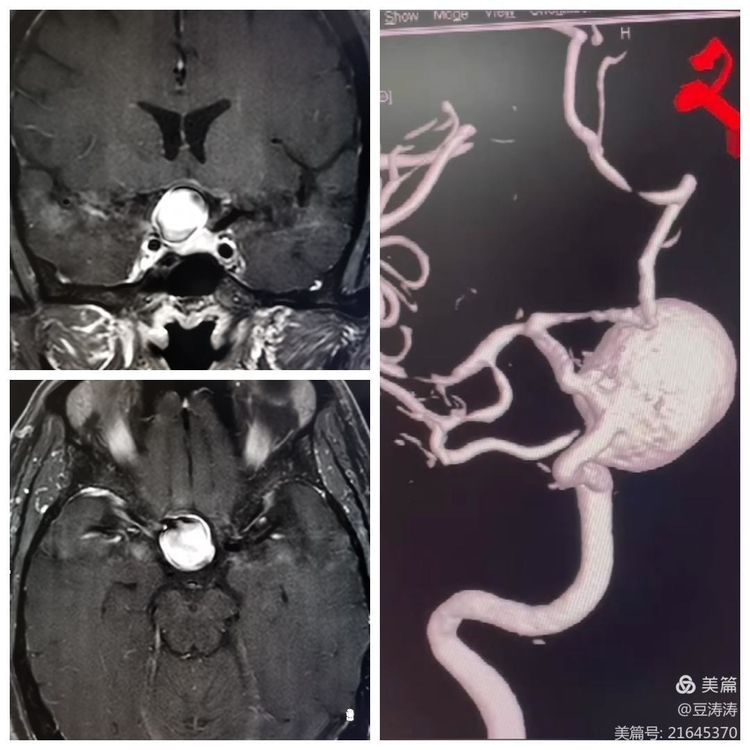

患者以视力模糊主诉入院。诊断颅内大动脉瘤。

正侧位及工作位造影。

动脉瘤3D重建